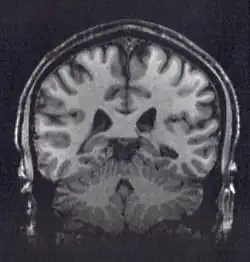

Un número de métodos han sido usados en la investigación de la confluencia de procesos neurales y sociales (importados desde la técnicas comportamentales, la psicología social, la psicología cognitiva y la neuropsicología) asociada con una variedad de técnicas neurobiológicas que incluyen Resonancia Magnética Funcional, Estimulación Magnética Transcraneal, Potenciales Relacionados con Eventos, Electrocardiogramas, Electromiogramas, endocrinología, respuesta galvánica de la piel, y estudio en pacientes con lesiones cerebrales focales.[5][6][7] Los modelos de investigación con animales son también importantes en la investigación de estructuras, circuitos y procesos cerebrales específicos (ejemplo., el sistema de recompensa y la adicción a las drogas). Adicionalmente, importante elaborar un metaanálisis es cuantitativo que aborde desde la idiosincrasia de los estudios individuales hasta las investigaciones en neurodesarrollo, lo que podría contribuir a la comprensión a la asociación entre el cerebro y el comportamiento.[8][9]